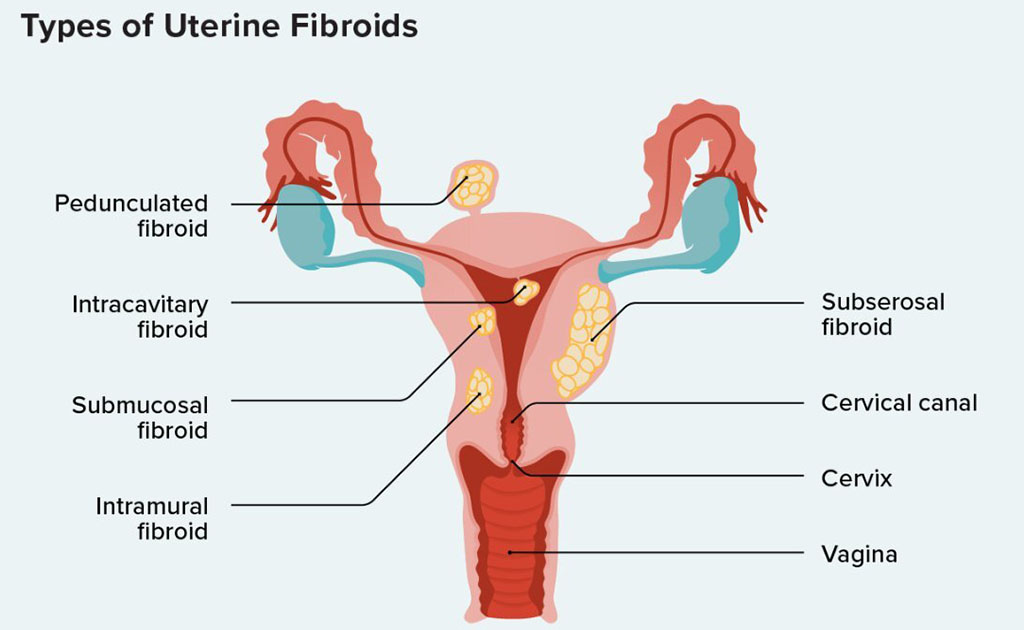

জরায়ুর ফাইব্রয়েড টিউমার কি প্রেগনেন্সির জটিলতা বাড়িয়ে দিতে পারে?

0 SHARES Share Tweet ফাইব্রয়েড জরায়ুর একটি অতি পরিচিত টিউমার। ৩৫ বছরের বেশি বয়সী নারীদের প্রতি ১০০ জনে ৩৫ জনের এই টিউমার...